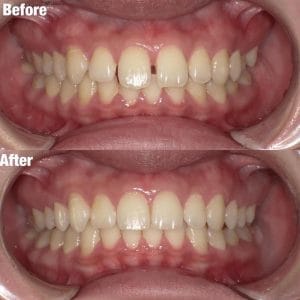

ワイヤー矯正

Case006 – ワイヤー矯正

片顎抜歯を行い、主に上の前歯の歯並びを矯正した症例です。

Case005 – ワイヤー矯正

Case004 – ワイヤー矯正

上下左右4本の抜歯を行い、全体の歯並びを矯正した症例です。

Case003 – ワイヤー矯正

Case002 – ワイヤー矯正

下の歯が前に出てしまう、いわゆる「受け口」を矯正した症例です。

Case001 – ワイヤー矯正